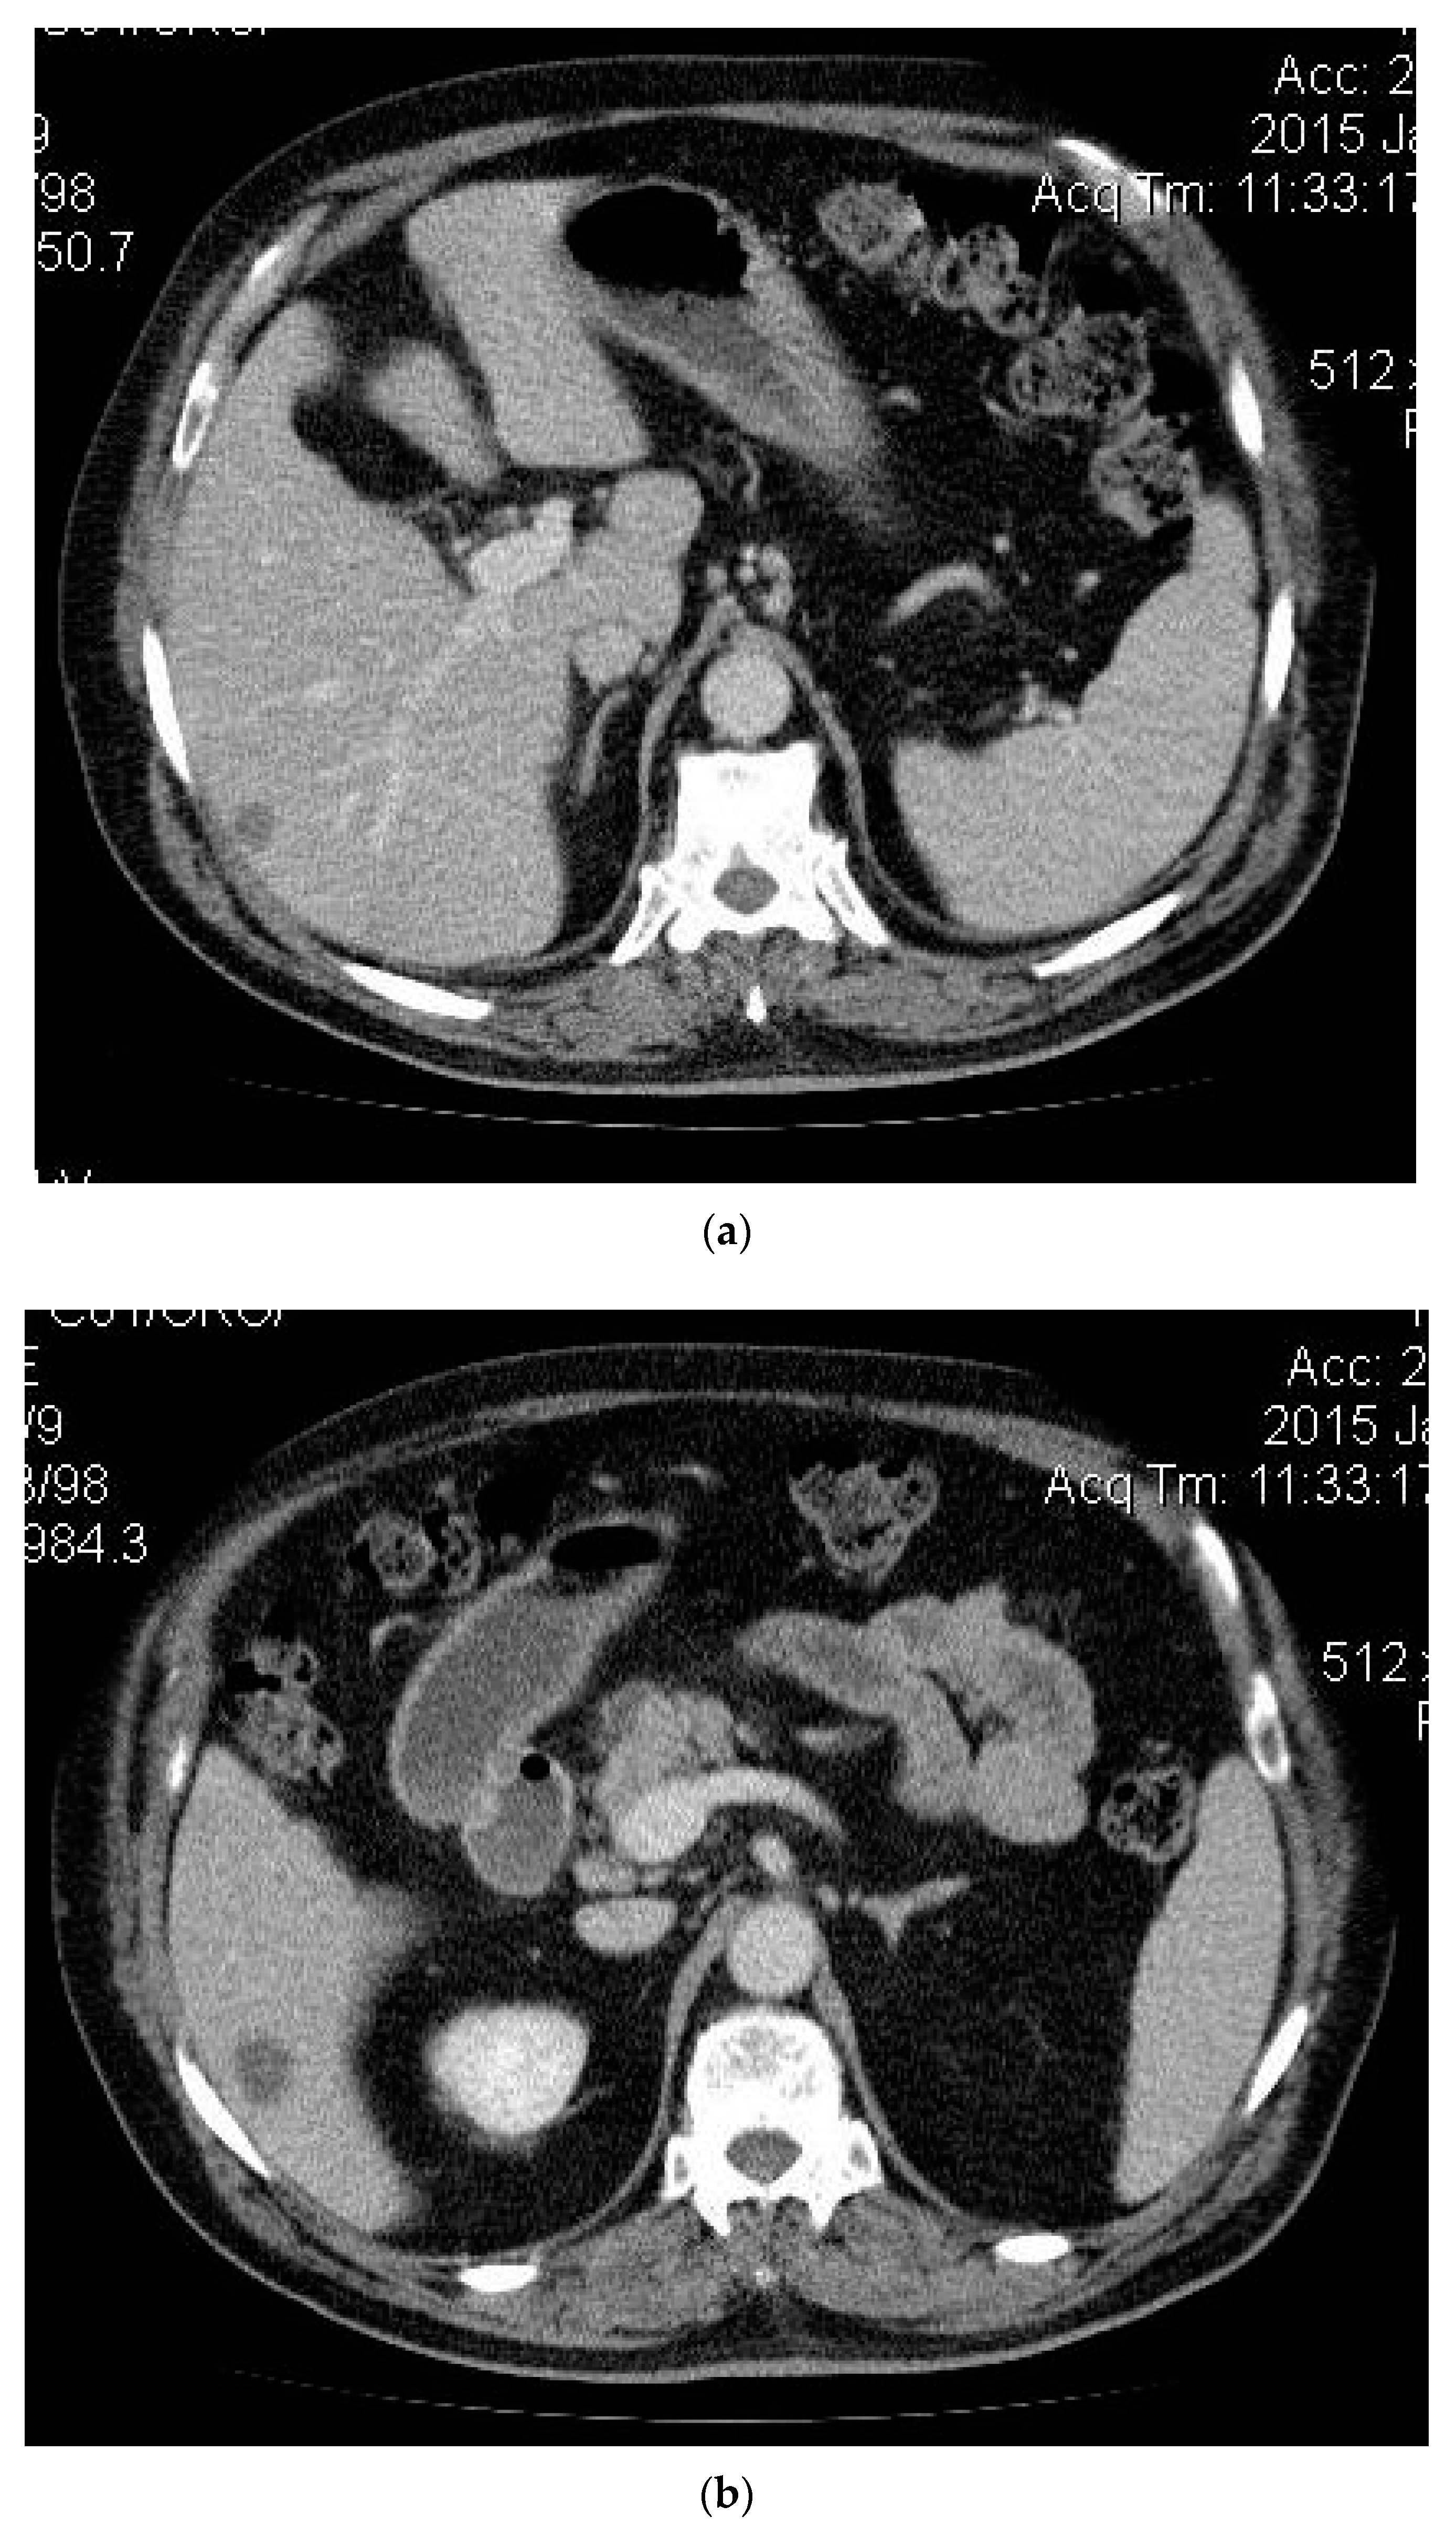

2. Case Presentation